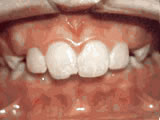

Missing lateral incisors

missing lateral incisors beforeBefore

missing lateral incisors afterAfter

This patient's lateral incisors were congenitally missing. She had braces for 20 months to move the teeth into their correct positions, then the missing teeth were replaced with bonded "Maryland" bridges.